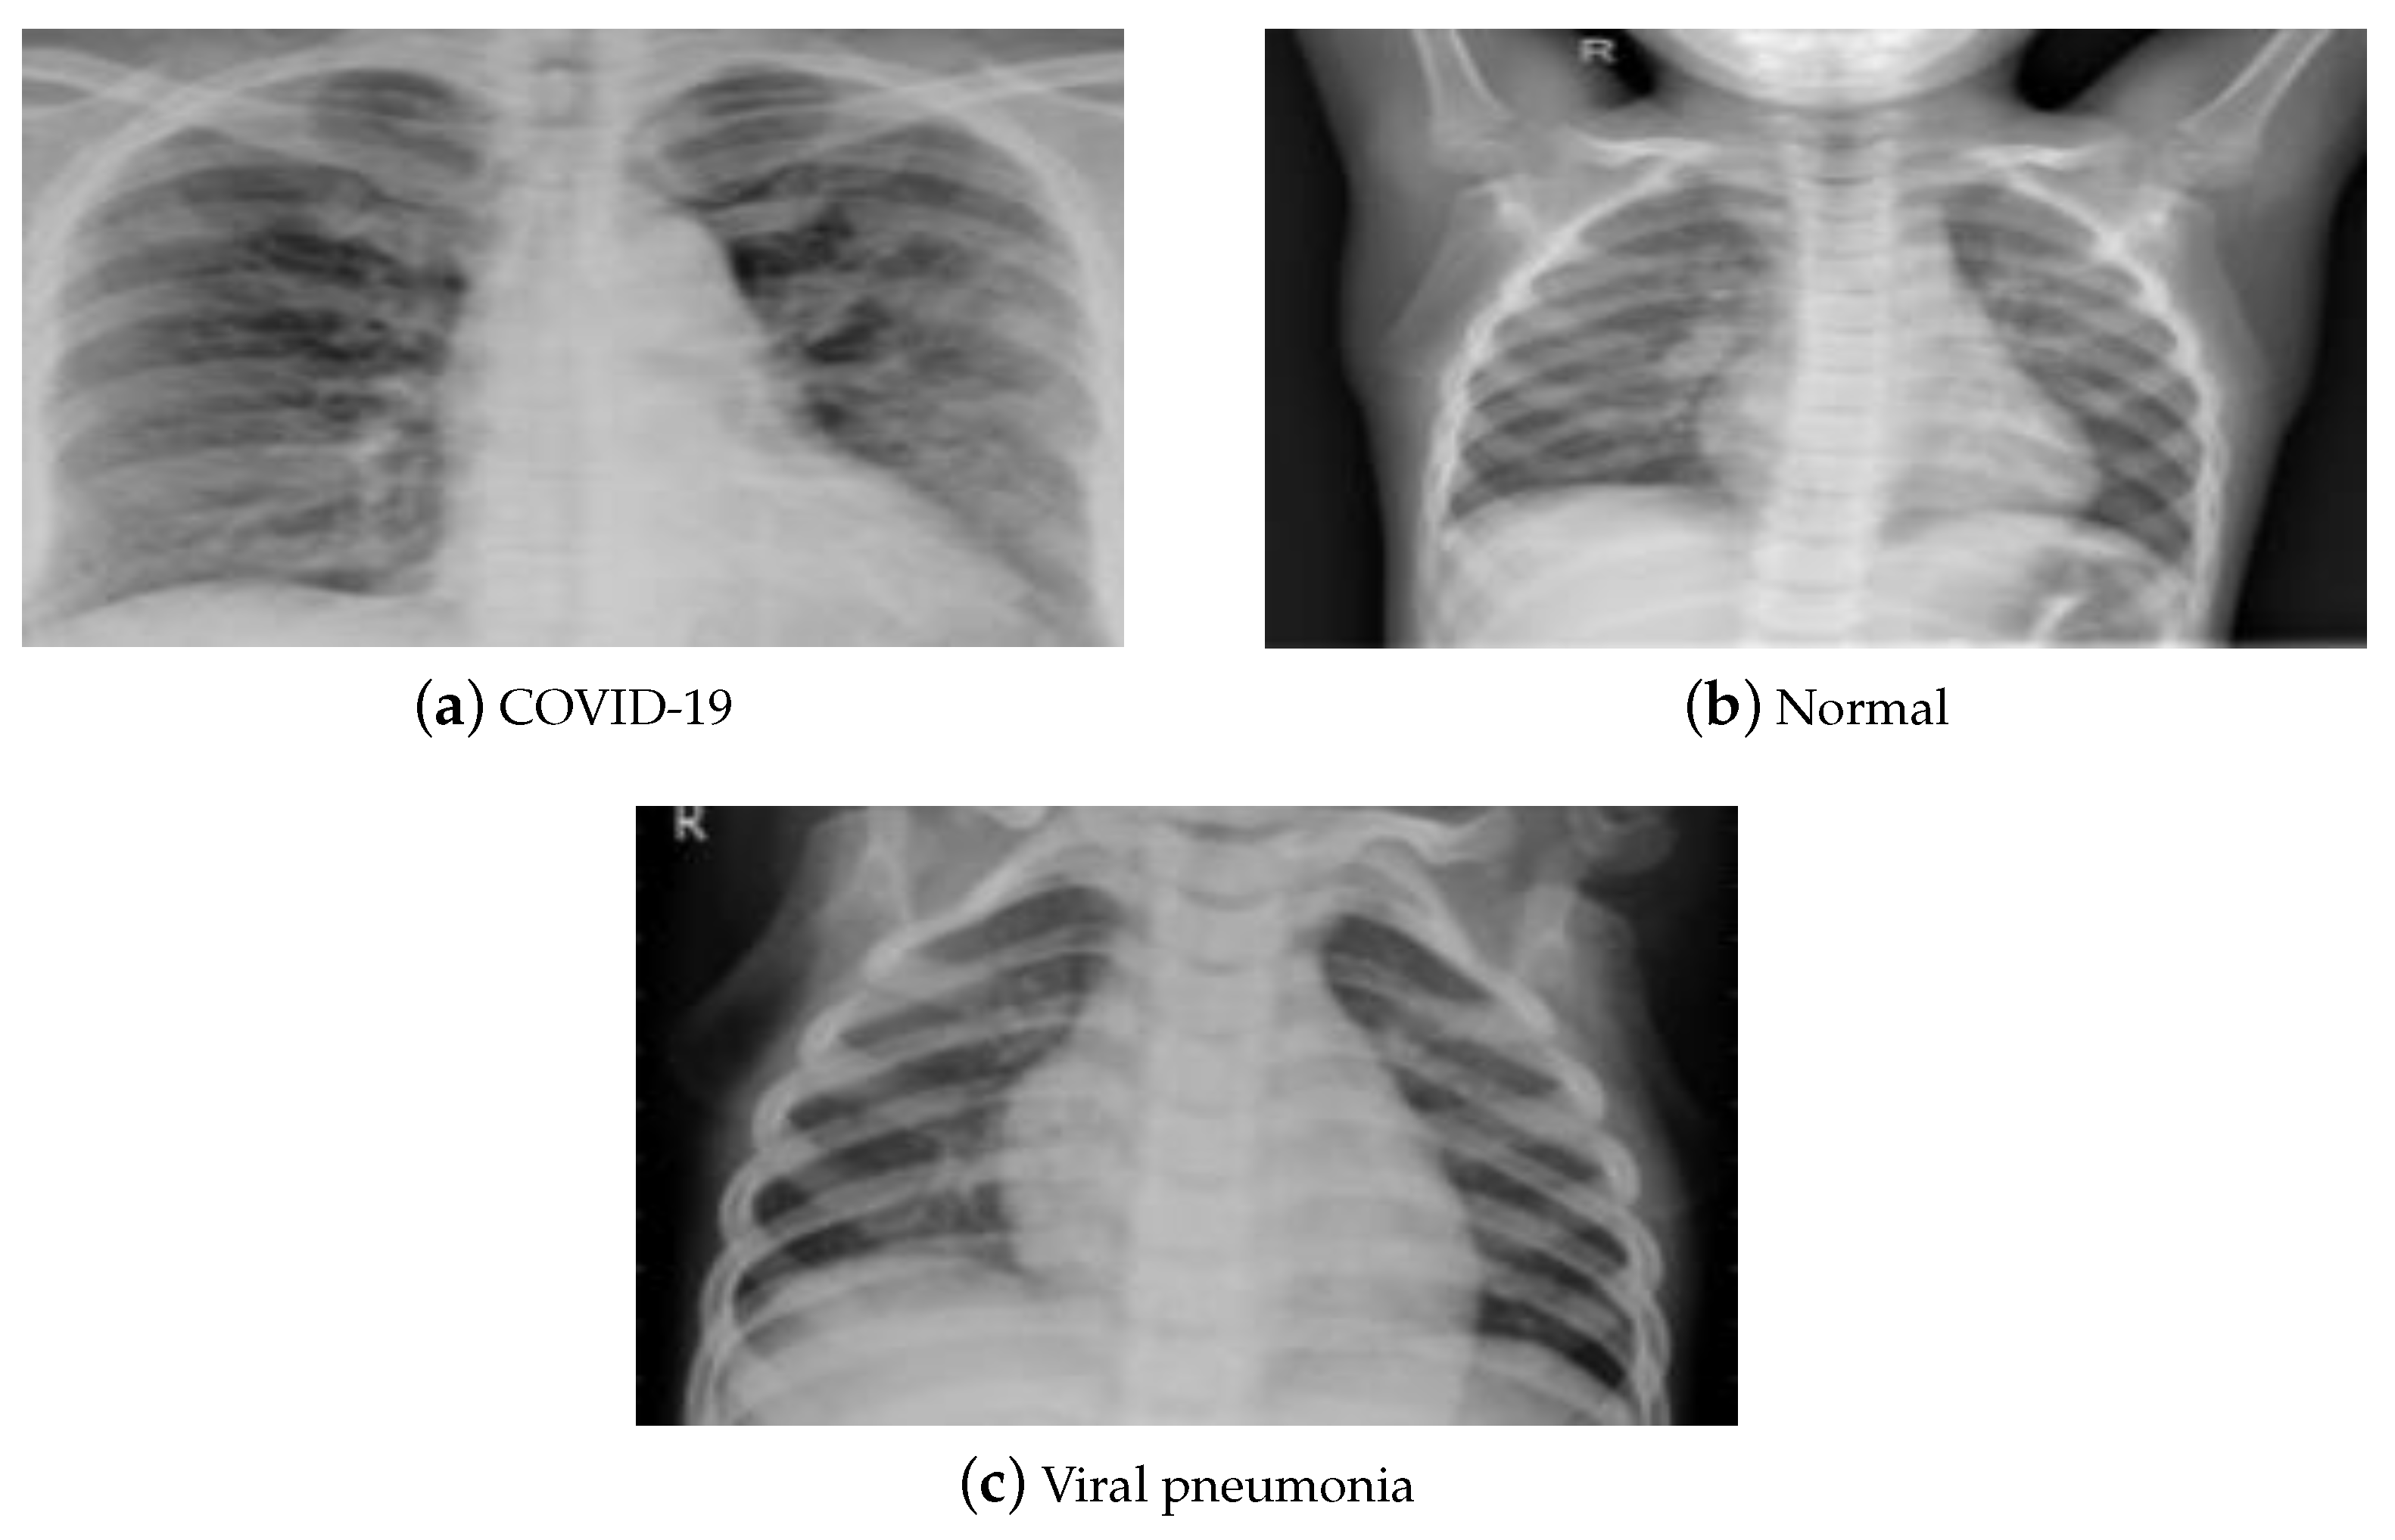

- Normalization: To improve the convergence of the training phase, input pixels to any AI system must have a normalized data distribution. To normalize an image, the distribution’s mean value is first subtracted from each pixel, then divided by the result by the standard deviation. Sample X-ray and CT images are shown in Figure 2 before (on the left) and after (on the right) the preprocessing steps.